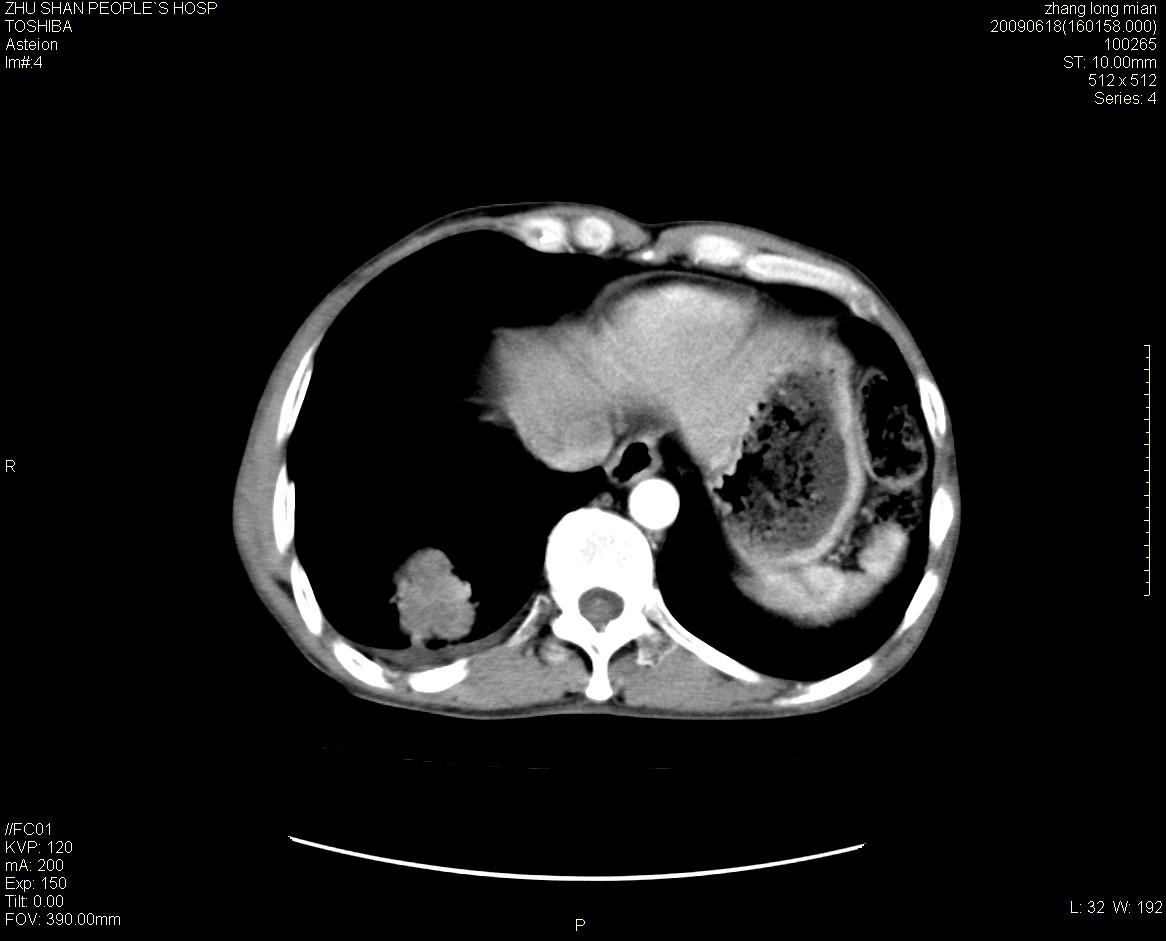

男性 65岁 胸片发现右下肺包块.诊断肺ca并纵隔转移没有问题吧!

右下肺见浅分叶状软组织块影,边缘有毛刺,其下部似见不完整偏心空洞影,邻近胸膜凹陷征,并胸腔积液。

增强见纵隔区气管隆突上下及左肺门区肿大淋巴结。左肺感染性病灶。